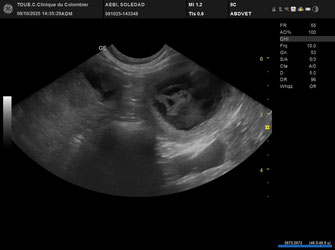

Echographie positive

Portée attendu pour mi-novembre 2025

Echographie positive

Portée attendu pour mi-novembre 2025